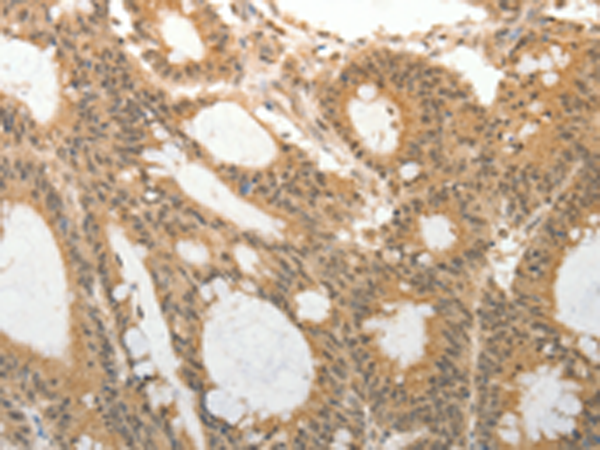

分类: 科研抗体货号: P11172别名:应用: IHC反应种属: Human, Mouse